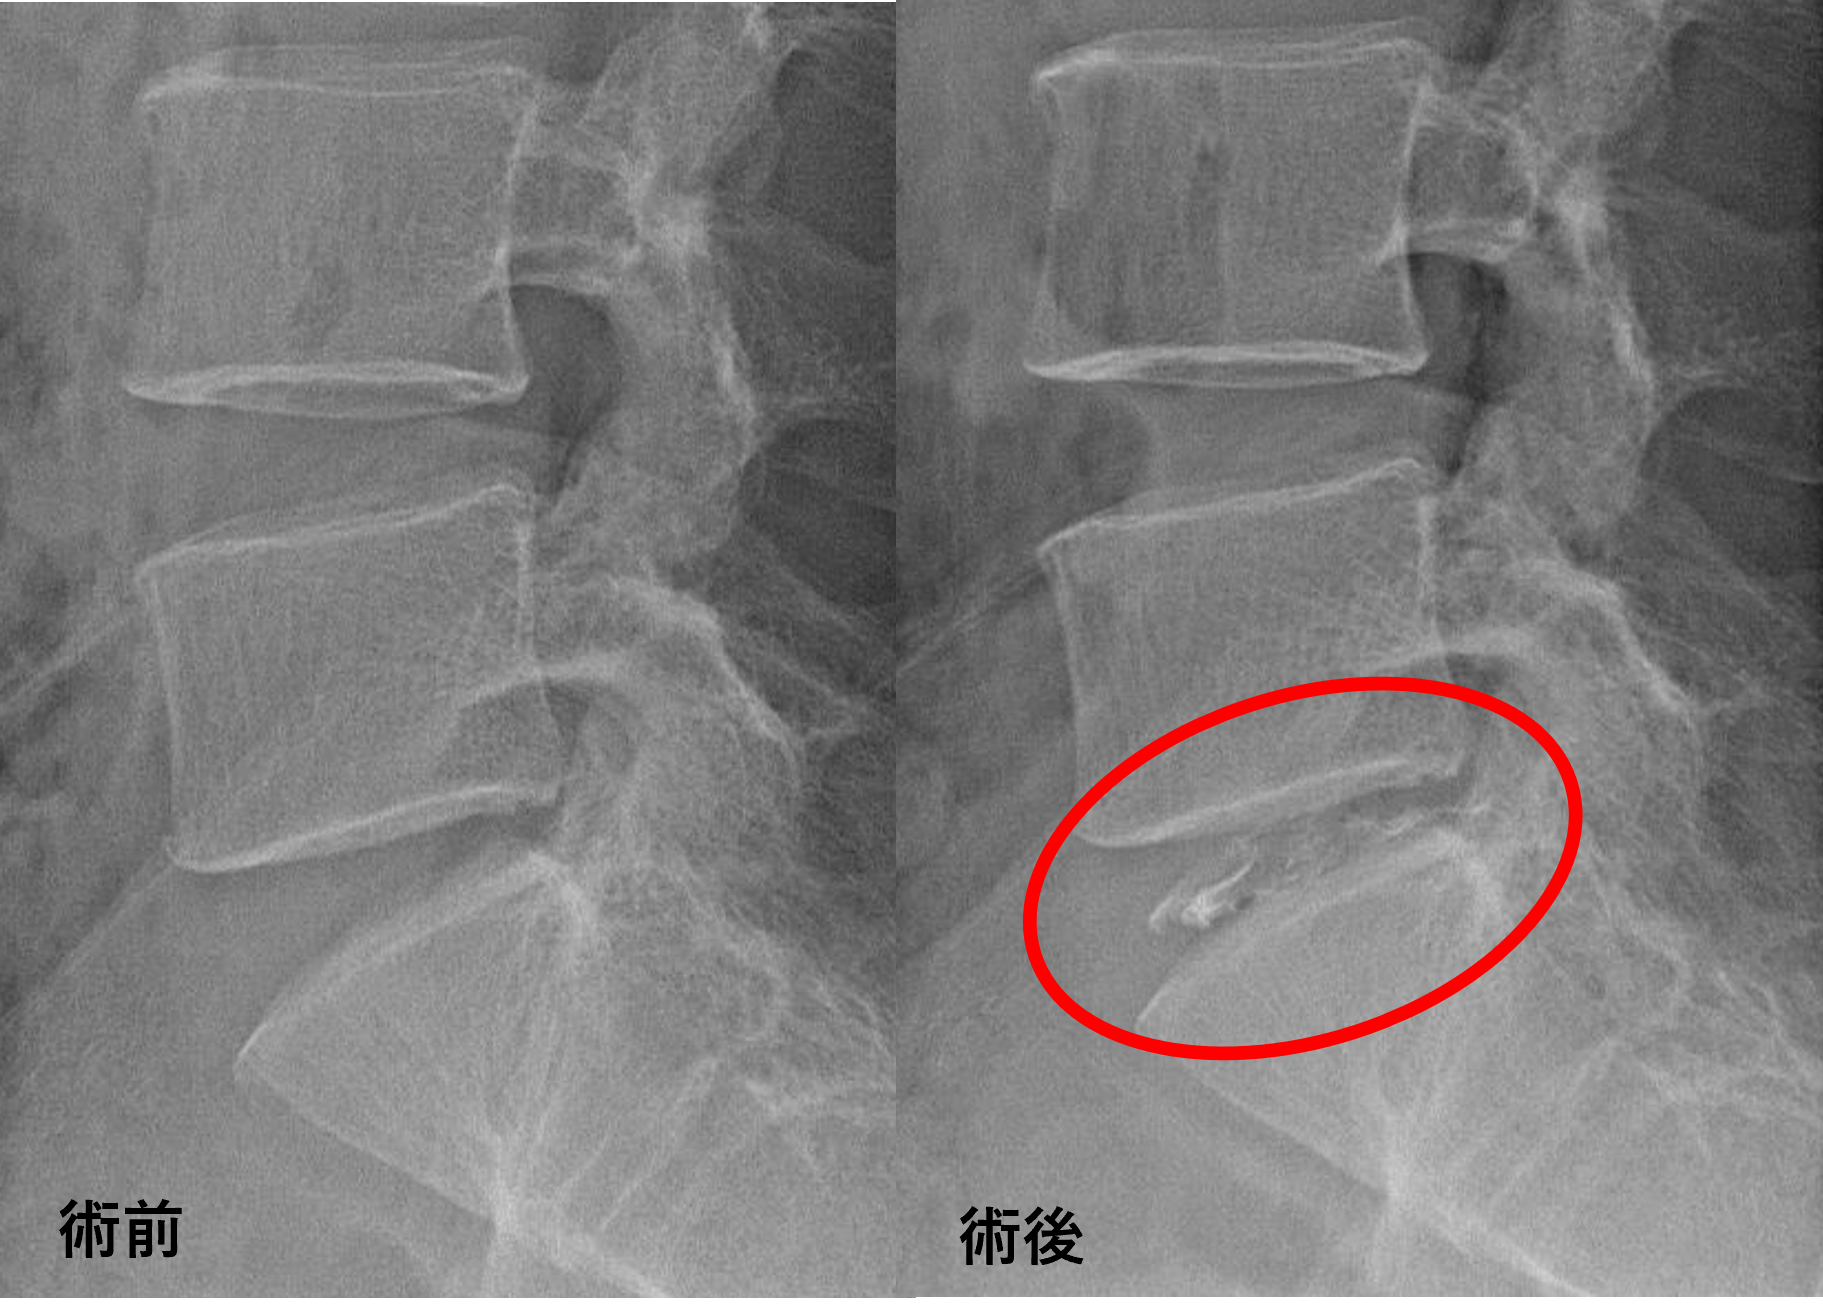

画像及び所見について

- L5/s – 椎間板変性、椎間板ヘルニア

以上のことが画像上認められました。

L5/sの椎間板所見による脊柱管の圧排が、症状の原因の可能性がもっとも高い。

患者様と相談の元、L5/sにセルゲル法を施行